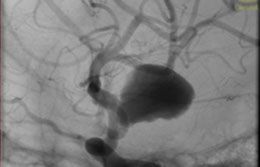

La paciente ingreso al Servicio de Hemodinamia el día martes 11 de febrero con un aneurisma cerebral gigante en la carótida izquierda y se le practicó una embolización; es decir una oclusión por dentro del mismo, donde se colocó un dispositivo denominado coils más un stent diversor de flujo. El procedimiento fue exitoso y contó con la colaboración de médicos neurointervencionistas del Instituto Oulton de la Ciudad de Córdoba.